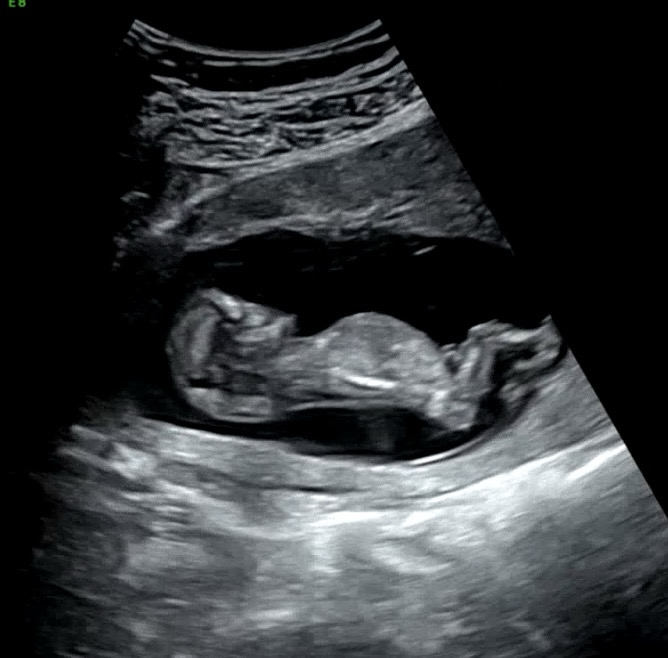

12주 성별 각도법 봐주세요🥹

각도법 고수님들 성별 투표 부탁드려요…!!!! 니프티 결과 나올때까지 기다리기가 힘드네요ㅠㅠㅎㅎㅎ